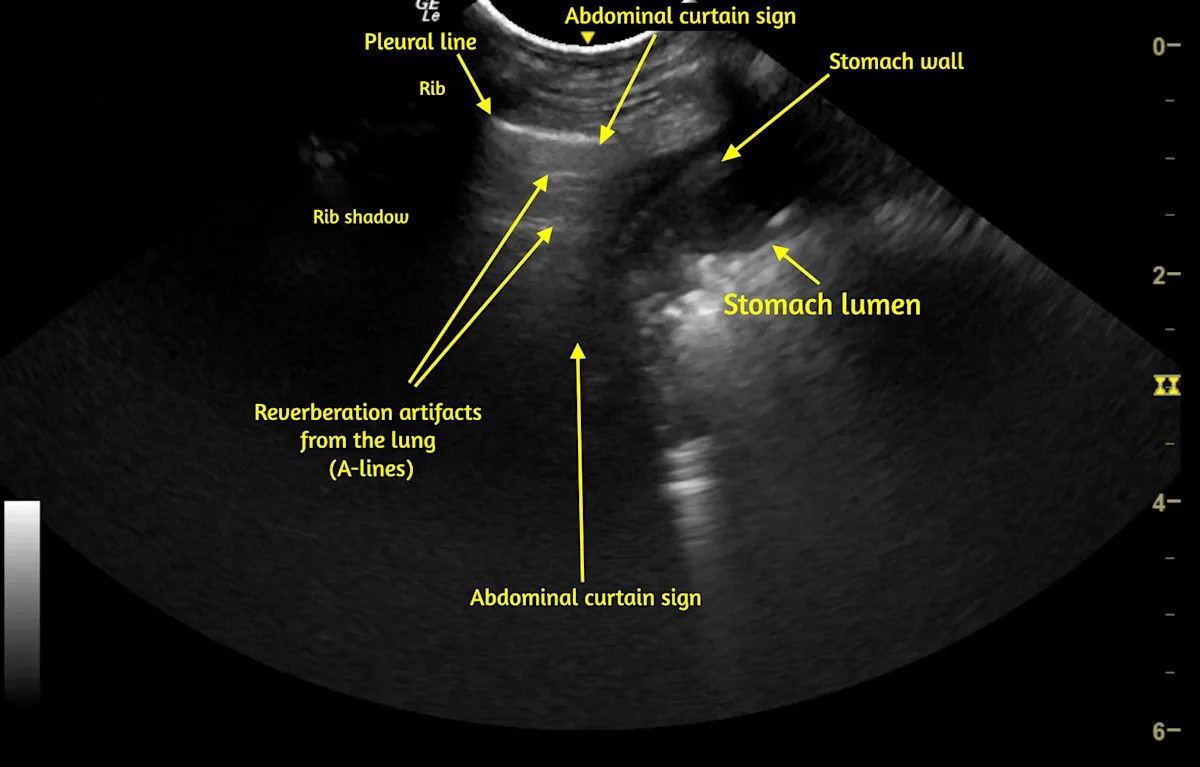

Familiarity with normal sonoanatomy, machine functions, image optimization, and sonographic artifacts that can result in false-positive or false-negative POCUS findings is also important. For example, abdominal structures below the caudal ribs can be confused with lung or pleural space pathology (Video 1), and rib or GI gas shadowing can obscure underlying structures, including pathology.

VIDEO 1 Pleural space and lung POCUS shows the left caudal lung border between the lung and abdomen. The vertical line (caudal lung border) that shifts cranially and caudally with respirations is the abdominal curtain sign. Caudal to the curtain sign, a small amount of liver is visible within the abdomen, followed by the stomach wall and gas and ingesta within the stomach lumen. The stomach wall can be misinterpreted as pleural effusion or stomach contents misinterpreted as lung consolidation if the operator is not familiar with the curtain sign. A labeled still image from the video is available below.